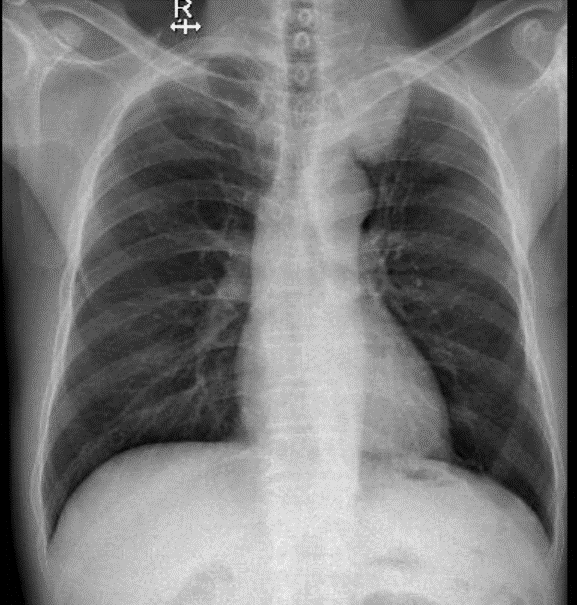

Hãy phân tích tình huống Nam 68 tuổi

1-Hình ảnh u đỉnh phổi trái, chẩn đoán phân biệt với u trung thất sau